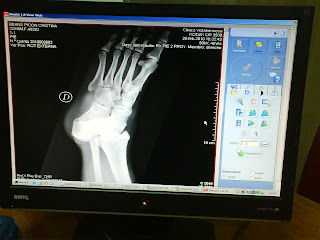

doesn't look like a foot? allow me:

Oh, and just to reassure you there isn't an Easter egg or an Alien growing out of my foot:

don't I have pretty bones? :p